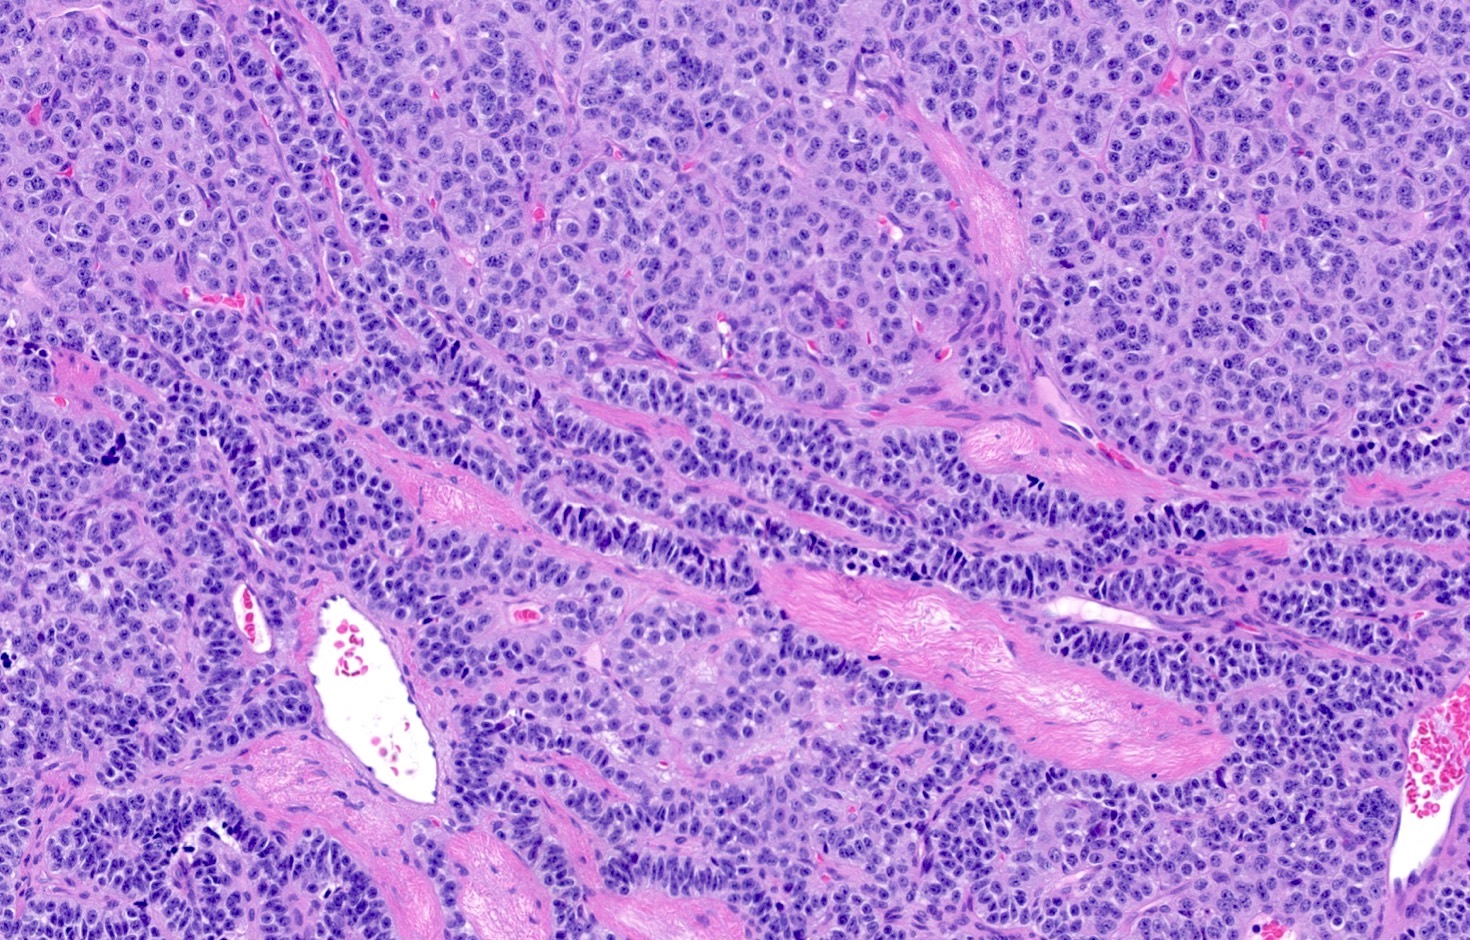

Microscopic (histologic) description

- Diagnostic criteria

- Neuroendocrine tumor with size ≥ 5 mm with < 2 mitoses/2 mm2 and absence of necrosis

- Neuroendocrine growth pattern (organoid, trabecular, rosette formation, nested) or pseudoglandular, follicular and papillary growth

- Tumor cells are uniform with a polygonal shape, round to oval nuclei with salt and pepper chromatin as well as inconspicuous nucleoli and moderate to abundant eosinophilic cytoplasm

- Spindle cells and clear cell features can be seen

- Stroma is fine and highly vascularized; hyalinization, cartilage or bone formation are possible

- Reference: Curr Oncol 2018;25:S86

Microscopic (histologic) images

Contributed by Philippe Joubert, M.D., Ph.D., Jijgee Munkhdelger, M.D., Ph.D. and Andrey Bychkov, M.D., Ph.D.

A 55 year old woman had a lower left lobectomy showing a well circumscribed flesh colored tumor. Histologic details are shown in the image above. Regarding this entity, which of the following statements is true?

Practice answer #1

A. CDX2 is usually negative in the lung and is useful to differentiate from a metastasis of an intestinal origin. The image shows a tumor with a trabecular pattern and pseudorosettes. The stroma is highly vascularized. Tumor cells are monotonous with scant to moderate eosinophilic cytoplasm. Nuclei are round to oval with salt and pepper chromatin and inconspicuous nucleoli. No mitoses are seen. These features are consistent with a typical carcinoid lung tumor.

Ki67 immunostaining, counter to well differentiated neuroendocrine tumors from the gastrointestinal tract, is not essential to grade the tumor. The difference between typical and atypical tumor relies on mitosis count and the presence of necrosis. However, Ki67 is useful to differentiate from high grade neuroendocrine tumors (small cell and large cell neuroendocrine carcinomas) on small biopsies with artifacts. TTF1 is positive in only half of cases with a higher frequency in peripheral tumors. Rb expression is preserved in typical carcinoid lung tumors, unlike in small cell tumors.